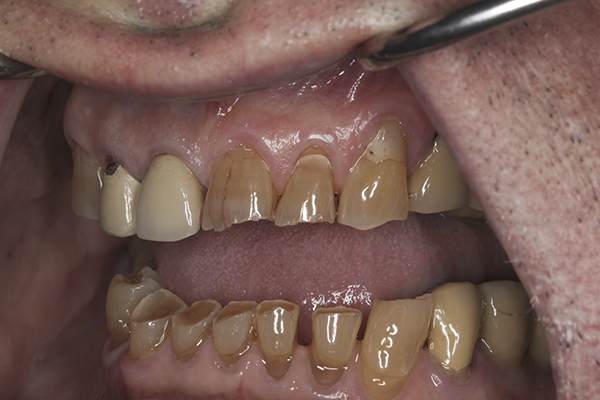

(10.) Preoperative anterior, closed view. Note the end-to-end occlusion of the anterior teeth and the wear on the incisors and centrals resulting in no anterior or canine guidance.

Figure 10

(13.) Preoperative anterior, close-up view.

Figure 13